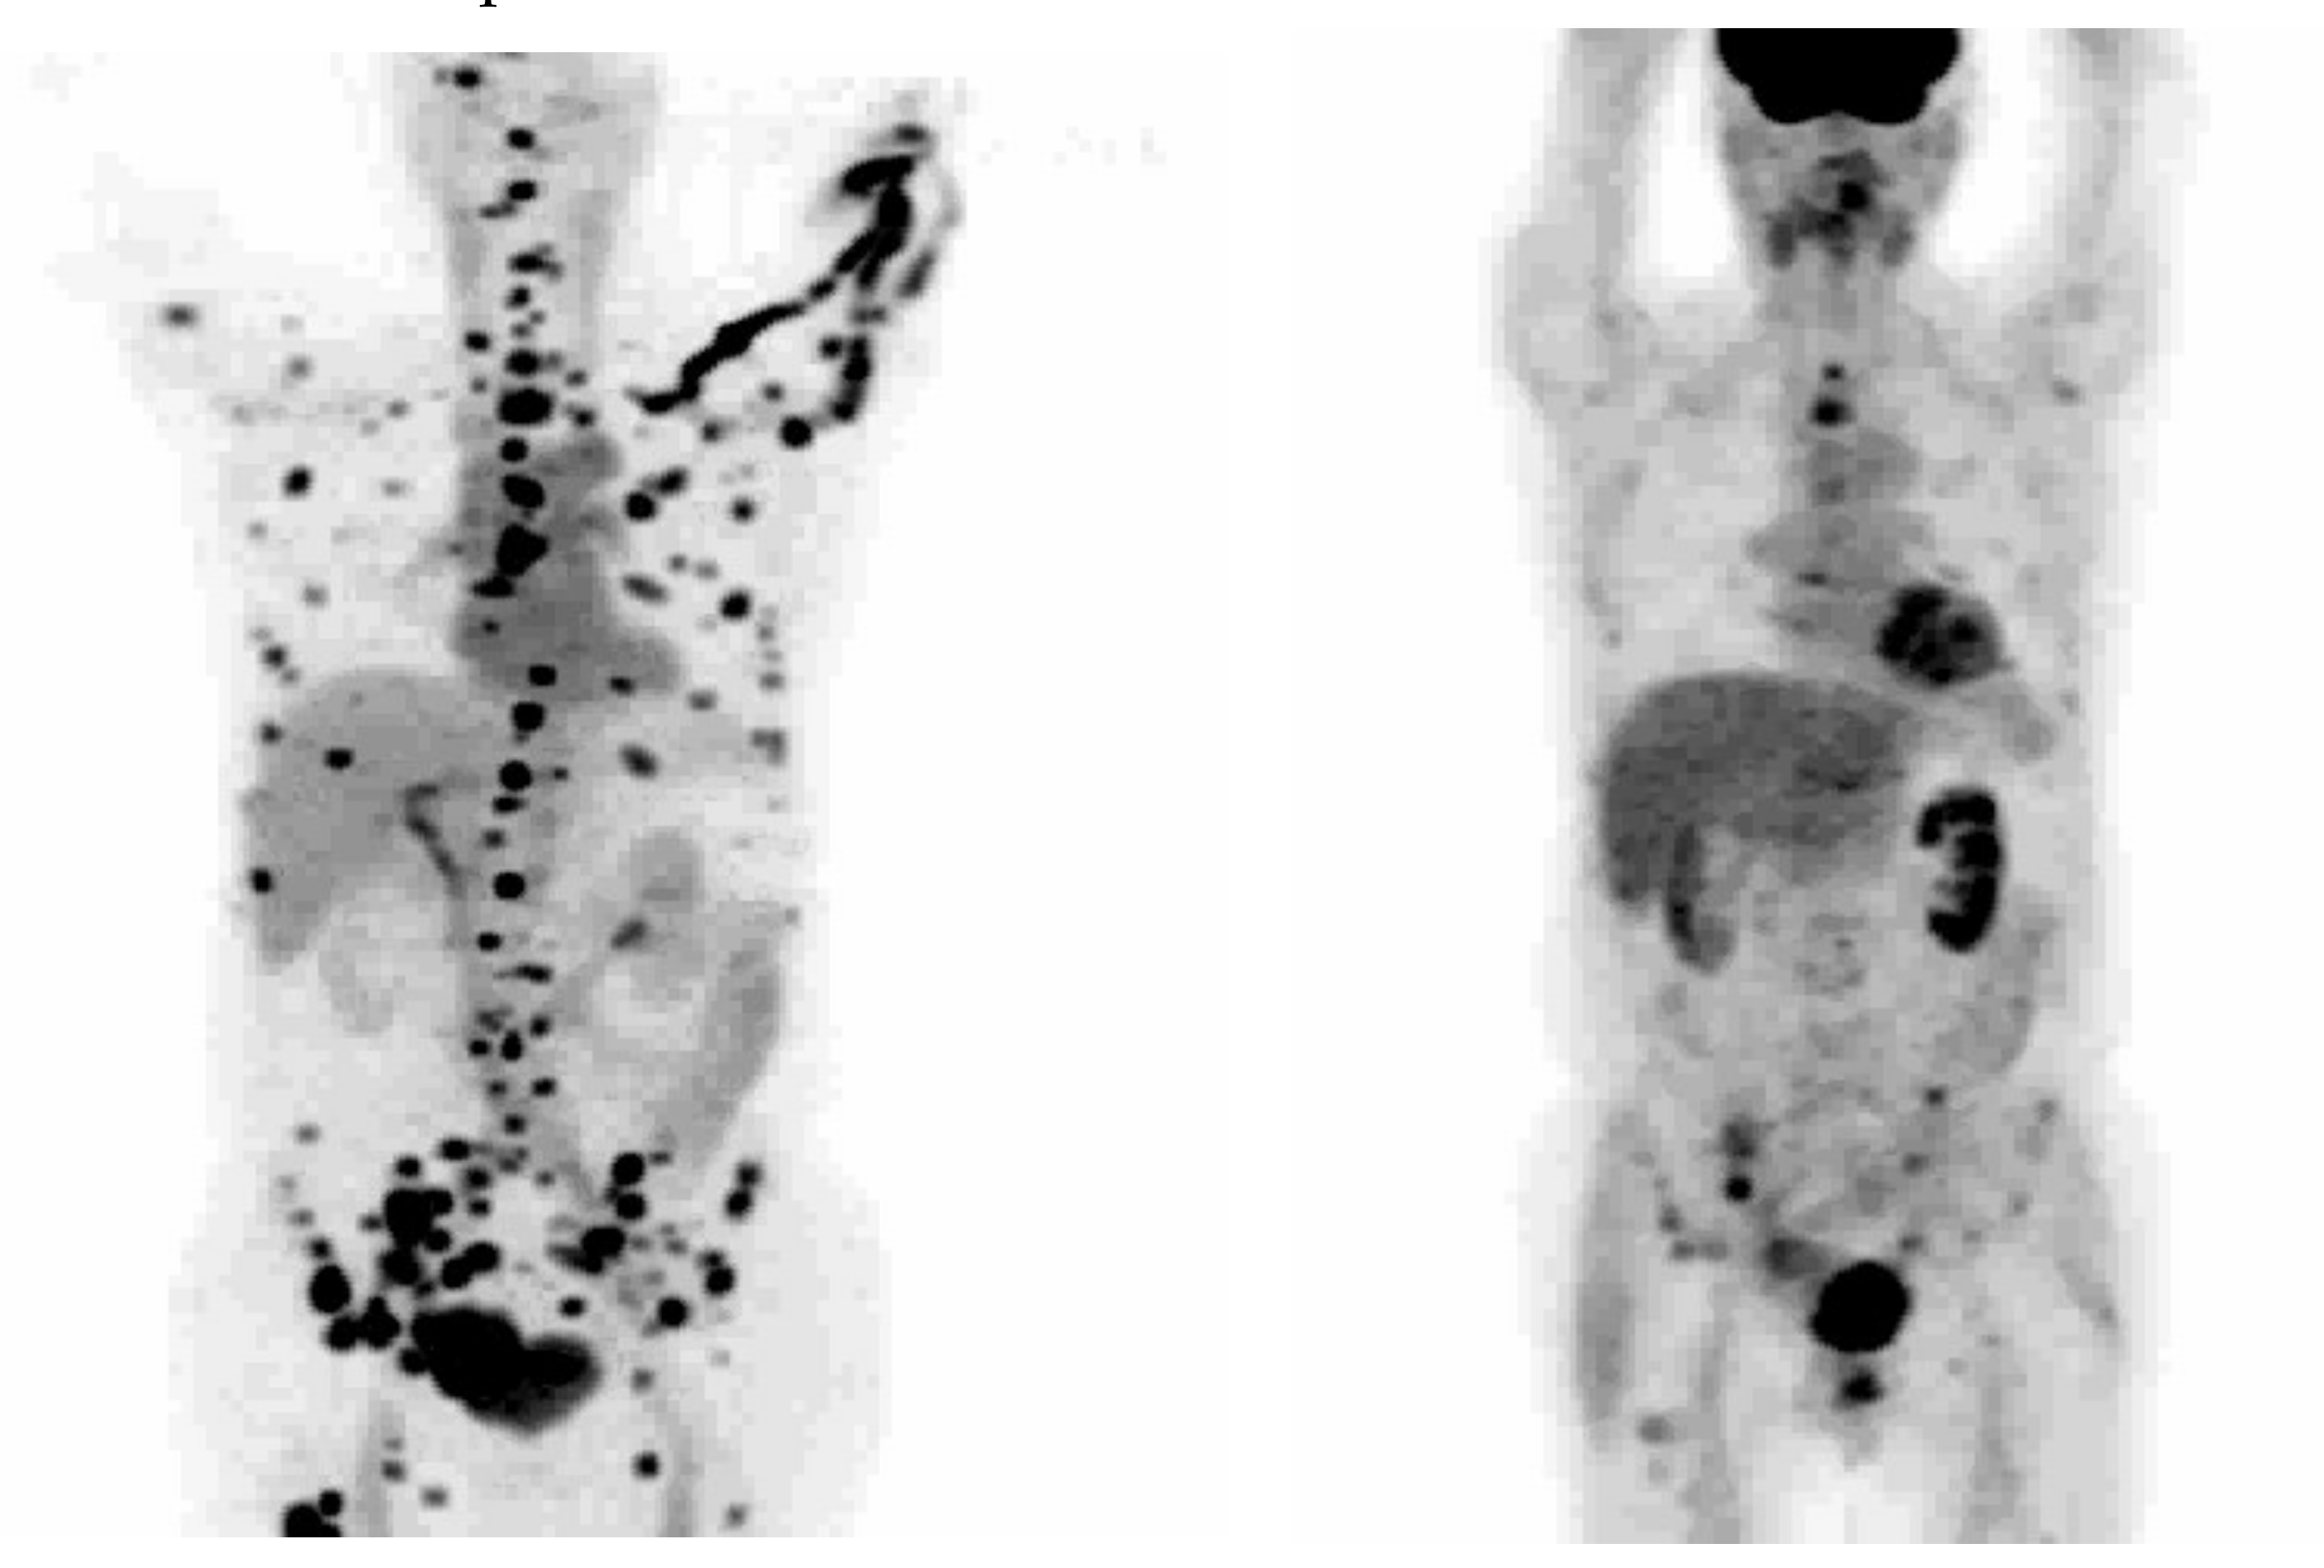

- Larson, S.M.; Morris, M.; Gunther, I.; Beattie, B.; Humm, J.L.; Akhurst, T.A.; Finn, R.D.; Erdi, Y.; Pentlow, K.; Dyke, J.; et al. Tumor localization of 16_-18F-fluoro-5alpha-dihydrotestosterone versus 18F-FDG in patients with progressive, metastatic prostate cancer. J. Nucl. Med. 2004, 45, 366–373. [Google Scholar]

- Fox, J.J.; Gavane, S.C.; Blanc-Autran, E.; Nehmeh, S.; Gönen, M.; Beattie, B.; Vargas, H.A.; Schöder, H.; Humm, J.L.; Fine, S.W.; et al. Positron Emission Tomography/Computed Tomography-Based Assessments of Androgen Receptor Expression and Glycolytic Activity as a Prognostic Biomarker for Metastatic Castration-Resistant Prostate Cancer. JAMA Oncol. 2018, 4, 217–224. [Google Scholar] [CrossRef]